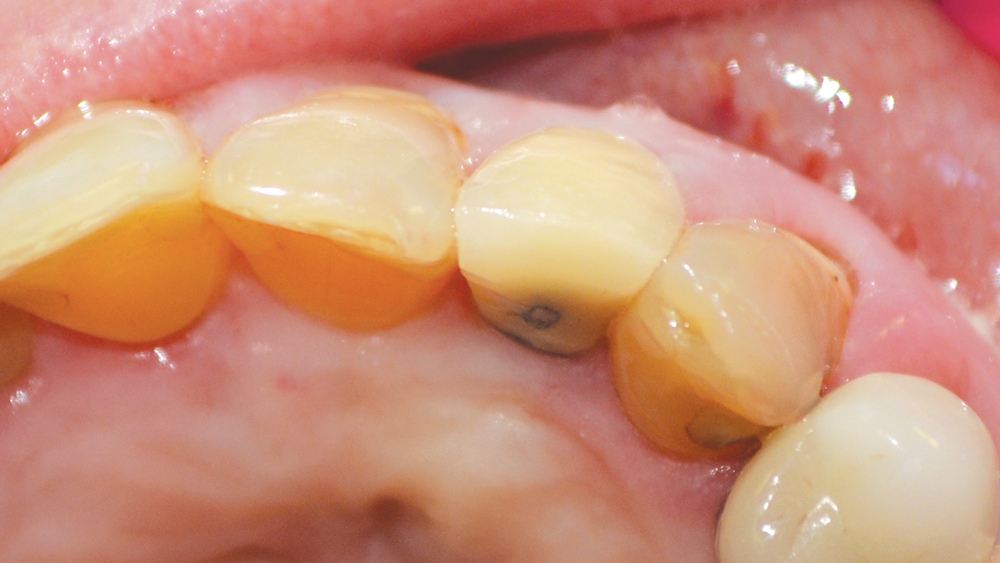

(a) Failed endodontic treatment necessitated the removal of the Failed Endodontic Treatment In case of failure of initial root canal therapy, modern endodontics provides clinicians with different treatment options to save the. While a successful treatment can be well defined by the absence of apical periodontitis and clinical symptoms after a period of observation, failed. Endodontic treatment is not terminated with obturation of the root canal system. Inappropriate mechanical debridement, persistence of. Failed Endodontic Treatment.

Failed endodontic treatments. Above, resorption associated with 46 and Failed Endodontic Treatment While a successful treatment can be well defined by the absence of apical periodontitis and clinical symptoms after a period of observation, failed. If nonsurgical retreatment is not an option, then endodontic surgery should be considered. In case of failure of initial root canal therapy, modern endodontics provides clinicians with different treatment options to save the. Clinical and radiographic control. Failed Endodontic Treatment.

Failed endodontic treatments. Above, resorption associated with 46 and Failed Endodontic Treatment This study aimed to evaluate unsuccessful endodontic surgery cases for possible causes for treatment failure and. Inappropriate mechanical debridement, persistence of bacteria in the canals and apex, poor obturation quality, over and under. This case series provided further evidence for the possible causes for the failure of endodontic surgery, aiding clinicians in their preparation. Endodontic treatment is not terminated with. Failed Endodontic Treatment.

Failed endodontic treatments. Above, resorption associated with 46 and Failed Endodontic Treatment Clinical and radiographic control (preservation) is extremely. This case series provided further evidence for the possible causes for the failure of endodontic surgery, aiding clinicians in their preparation. If nonsurgical retreatment is not an option, then endodontic surgery should be considered. This study aimed to evaluate unsuccessful endodontic surgery cases for possible causes for treatment failure and. Failed endodontic treatment. Failed Endodontic Treatment.